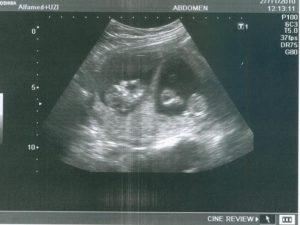

УЗИ при ЭКО назначается на раннем сроке — обычно через три недели после переноса эмбрионов. Начальный этап характеризуется повышенным риском отторжения плода. В это время актуальны мощная гормональная терапия и постоянный мониторинг. Первое УЗИ после ЭКО покажет:

1. в правильном ли месте прикрепился плод;

2. нет ли риска кровотечения из-за его положения (возможно в случае прикрепления вблизи шейки матки);

3. даст оценку развития будущего человека.

В этот же период начинается рост плаценты – уникального органа, обеспечивающего защиту и питание плода. Из трофобласта и эктодермы образуются амнион и хорион. Амниотическая полость заполняется околоплодными водами, а хорион начинает активно продуцировать ХГЧ. Размеры эмбриона достигают значения в 4 мм и его уже можно увидеть на УЗИ.

После проведения анализа на содержание в крови хорионического гонадотропина женщина уже может знать, что она носит в себе новую жизнь. Спустя 3 недели беременности, что происходит с плодом – можно разглядеть с помощью ультразвукового исследования.

На этом этапе эмбрион представляет собой крошечный шар с едва различимыми головным и хвостовым концами, окруженный плодным яйцом. УЗИ-диагностика на ранних сроках беременности проводится двумя способами:

Именно УЗИ на третьей неделе после введения эмбрионов является методом, позволяющим достоверно определить наличие беременности, так как ЭКО, к сожалению, не всегда может гарантировать удачный результат.

Кроме того с помощью ультразвукового сканирования можно увидеть:

• Количество жизнеспособных эмбрионов в матке;

• Место расположения плодного яйца;

• Изменения в яичниках.

Первое УЗИ является необычайно важным для исключения серьезных патологий в виде внематочной беременности, остановки развития плода, определения многоплодной беременности и необходимости дальнейшего проведения или коррекции поддерживающей терапии.